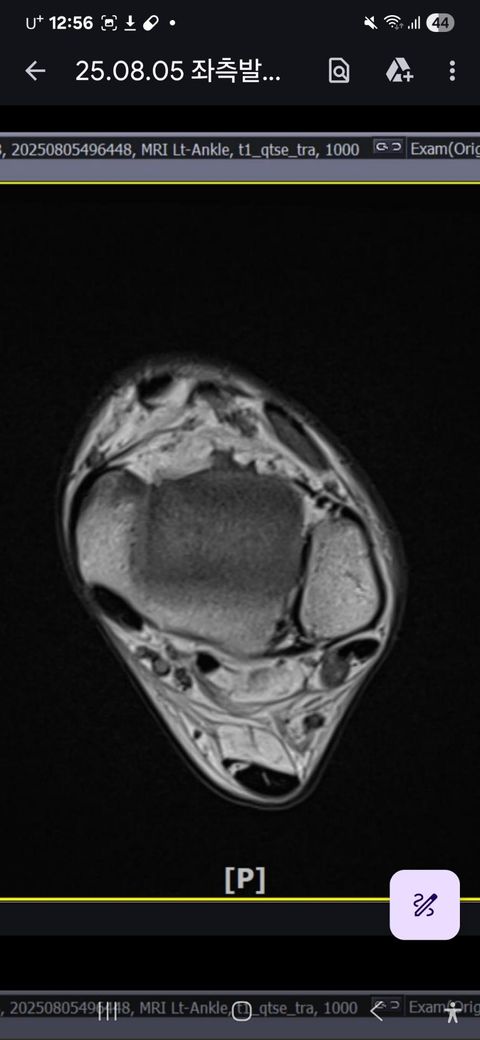

발목인대 상태 질문드립니다. (mri사진 첨부)

그래도 통증이 남아 8월 5일에 MRI를 촬영했는데, 병원에서는 “인대는 이어져 있고, 이 정도면 재활운동으로 호전될 것”이라는 설명을 들었습니다.

MRI 상 전거비인대와 발목 상태가 정말 회복 단계인지, 아니면 만성으로 넘어가는 건 아닌지 전문가분들의

의견을 듣고 싶습니다.

• 1번 째 사진

올려주신 mri를 보면 전거비인대는 연속성이 유지되고 있고 파열이나 큰 손상 흔적은 없어 재활로 회복 가능한 상태로 보입니다 다만 3개월 가까이 활동 시 통증과 미열감이 남아 있는 것은 조직 회복이 아직 완전히 끝나지 않았거나 주변 연부조직 관절 움직임 제한 등으로 인한 과민 반응일 수 있습니다.

초음파와 비교하면 mri 상으로 인대 연속성이 확인되므로 심각한 악화나 재파열은 아닌 것으로 판단됩니다